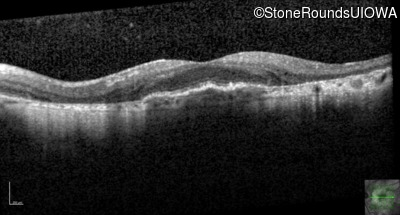

Optical Coherence Tomography - Left - 20/40 +1

Exemplar / OCT Stack

OCT Stack